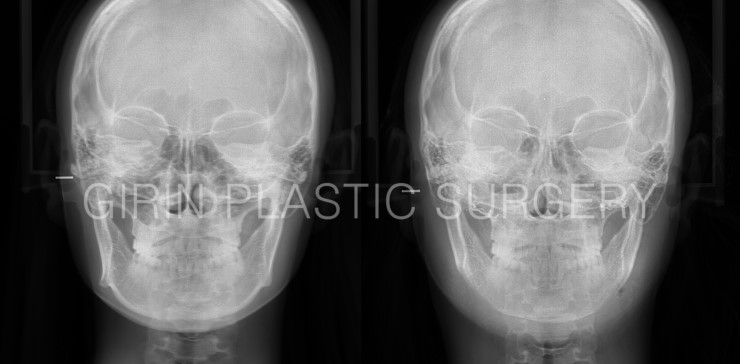

정면엑스레이